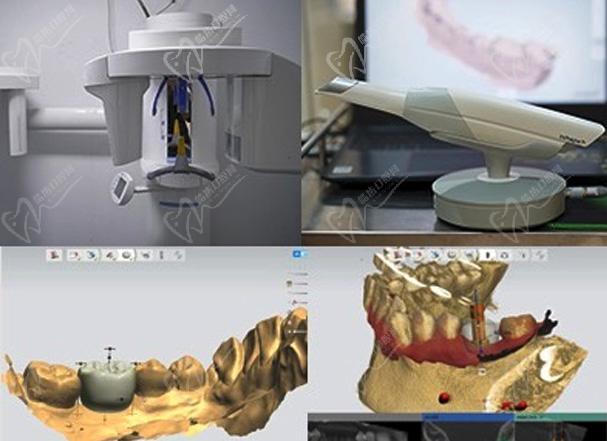

深圳福华口腔数字化技术——提供舒适、省时、安全的口腔诊疗技术

数字化种植

通过锥形束CT数字化叠加扫描技术即可以全方位获取头颅、牙骨情况,及牙骨密度、高度、厚度、宽度等核心数据,可以极大的辅助种植医生进行准确诊断和设计,从而为全口/半口无牙颌,单颗、多颗牙缺失,牙齿伤断和牙列坏损等患者提供优质的种植牙解决方案。

数字化矫正

通过iTero口扫仪获取患者全口数据,可亲自见证矫正后模拟效果图以及牙颌的变化过程,并可评估牙齿矫治进度,成像快速、操作直观、可视化效果出色、互操作能力强、高精度。随时调整患者佩戴进度。

数字化修复

借助计算机综合运用美学原理进行牙齿美容,面部美学分析,数字面弓确定中线、笑线、牙长轴线、外形顶点,确定前牙龈缘高度、长宽比例、大小比例绘制牙齿形态曲线完成美学设计,为您量身打造个性化微笑设计。